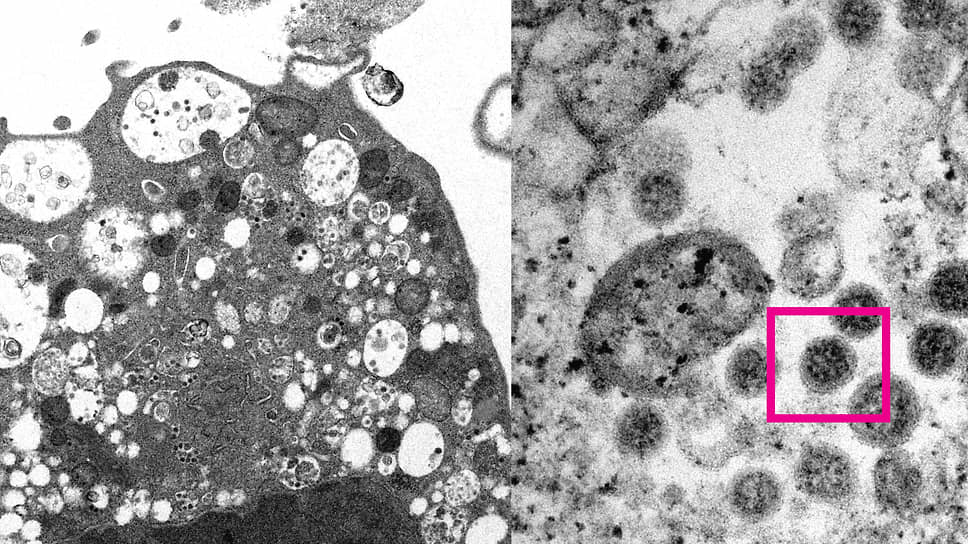

Изображение штамма коронавируса «омикрон»

Фото: med.hku.hk